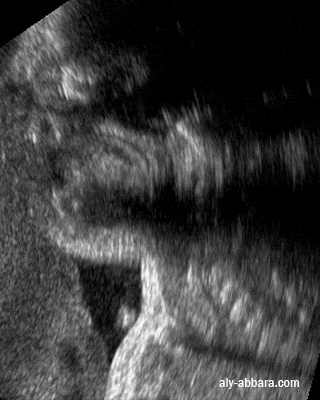

• Image échographique statique montrant une coupe sagittale passant par la cavité buccale et le pharynx, elle met en évidence la position anatomique et le rôle physiologique de la luette, un appendice charnu, mobile et contractile, prolongeant le bord postérieur du voile du palais et qui contribue à la fermeture du rhinopharynx pendant la déglutition.

• Fœtus de 32 semaines d'aménorrhée.